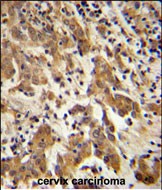

- GKAP1 Antibody (C-term) (Cat. #P30684) immunohistochemistry analysis in formalin fixed and paraffin embedded human cervix carcinoma followed by peroxidase conjugation of the secondary antibody and DAB staining. This data demonstrates the use of the GKAP1 Antibody (C-term) for immunohistochemistry. Clinical relevance has not been evaluated.